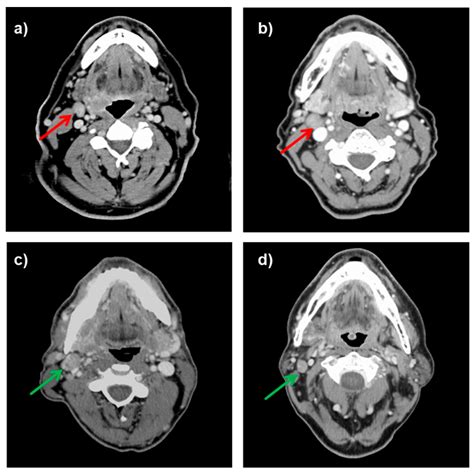

The human lymphatic system is an extensive network of vessels and nodes that helps maintain fluid balance and combats infections. The neck, specifically, is a high-traffic area for this system, housing hundreds of lymph nodes. The posterior cervical nodes form a chain situated along the posterior border of the sternocleidomastoid muscle—the large muscle that runs from your collarbone up to behind your ear. They extend toward the trapezius muscle in the upper back and shoulder area.

Because of their location, these nodes are primarily responsible for draining lymph fluid from the posterior scalp, the back of the neck, and parts of the upper back. When your body detects an infection in these specific areas, lymphocytes (white blood cells) multiply within the node to fight the pathogen. This proliferation causes the node to enlarge, resulting in what medical professionals call lymphadenopathy.